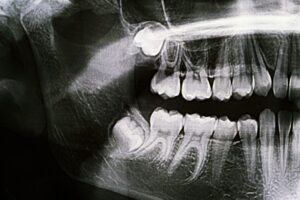

Your Oral Surgeon in Elmhurst on Wisdom Teeth

Your Oral Surgeon in Elmhurst on Wisdom Teeth Your Guide to Wisdom Teeth and When Removal Is Necessary Wisdom teeth are the third set of